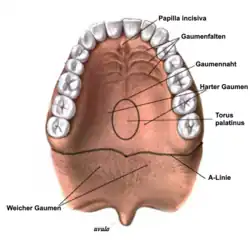

Die Weichteile im Mund können die Prothese bei verschiedenen Mund- und Zungenbewegungen lockern oder abhebeln. Die Prothese muss deshalb den diversen Muskelbändern einen Bewegungsspielraum lassen, wie beispielsweise dem Zungenbändchen oder den Lippen- und Wangenbändchen. Im Unterkiefer wird mit der Funktionsabformung auch der Bewegungsspielraum des Mundbodens berücksichtigt, da der Mundboden sich im Zusammenspiel mit der Zunge hebt und senkt. Die Prothese darf dadurch nicht vom Unterkiefer abgehoben und ausgehebelt werden. Der Prothesenrand muss gleichzeitig die Prothese weitgehend abdichten, was die Zielsetzung der mukodynamischen Abformung ist. Hierbei wird zwischen dem äußeren und inneren Ventilrand der Prothese unterschieden. Der innere Ventilrand befindet sich zwischen der Mukosa (Schleimhaut) des Alveolarkamms und dem inneren Rand der Prothesenbasis. Der äußere Ventilrand befindet sich zwischen dem Außenrand der Prothese und der Wangenschleimhaut. Im Oberkiefer wird am Übergang des weichen zum harten Gaumen (durch Radieren der sogenannten A-Linie am Gipsmodell) ein distaler (hinterer) Abschlussrand der Prothese erzeugt. Die A-Linie ist danach benannt, dass sich bei der Aussprache des Lautes „A“ der weiche Gaumen nach unten bewegt und dadurch für den Behandler sichtbar wird. Der Rand kann anschließend mit einem Stift markiert werden und bildet sich auf der Abformmasse ab. Dadurch kann der Zahntechniker die A-Linie nach Herstellung des Gipsmodells des Oberkiefers erkennen.[11] Mit einem speziellen Abformmaterial (F.I.T.T. Functional Impression Tissue Toner) ist eine Langzeit-Funktionsabformung bei schwierigen Kieferverhältnissen möglich. Das Material kann mehrere Tage lang getragen werden, sowohl um die Wiederherstellung von verletztem Gewebe zu unterstützen, als auch eine Abformung während des täglichen Gebrauchs durchzuführen.

Torus palatinus

Der Torus palatinus, eine Exostose (knöcherner Wulst) in der Mitte des sogenannten harten Gaumens, kann den Halt einer Totalprothese im Oberkiefer erschweren, da die umliegende Schleimhaut nachgiebig ist, der Torus palatinus jedoch nicht. Daher kann die Prothese über den Torus nach rechts und links schaukeln. Dem kann dadurch abgeholfen werden, dass der Torus „entlastet“ wird. Hierzu wird bei der Herstellung der Prothese eine Zinnfolie von etwa 1 bis 2 mm Stärke als Platzhalter auf dem Gipsmodell über den Bereich des Torus gelegt, wodurch der Torus bei der fertiggestellten Prothese hohl gelegt sein wird. Diese Hohllegung kann auch – eingeschränkt – nachträglich durch Ausschleifen dieses Prothesenbereichs erfolgen. Bei Ausübung des Kaudrucks gibt dann zunächst die umliegende Schleimhaut nach, bevor die Prothese mit dem Torus in Kontakt tritt.[44] Die Inzidenz (Häufigkeit) des Torus palatinus und des Torus mandibularis (im Unterkiefer) in der Bevölkerung wird mit etwa 30 % angegeben.[45]